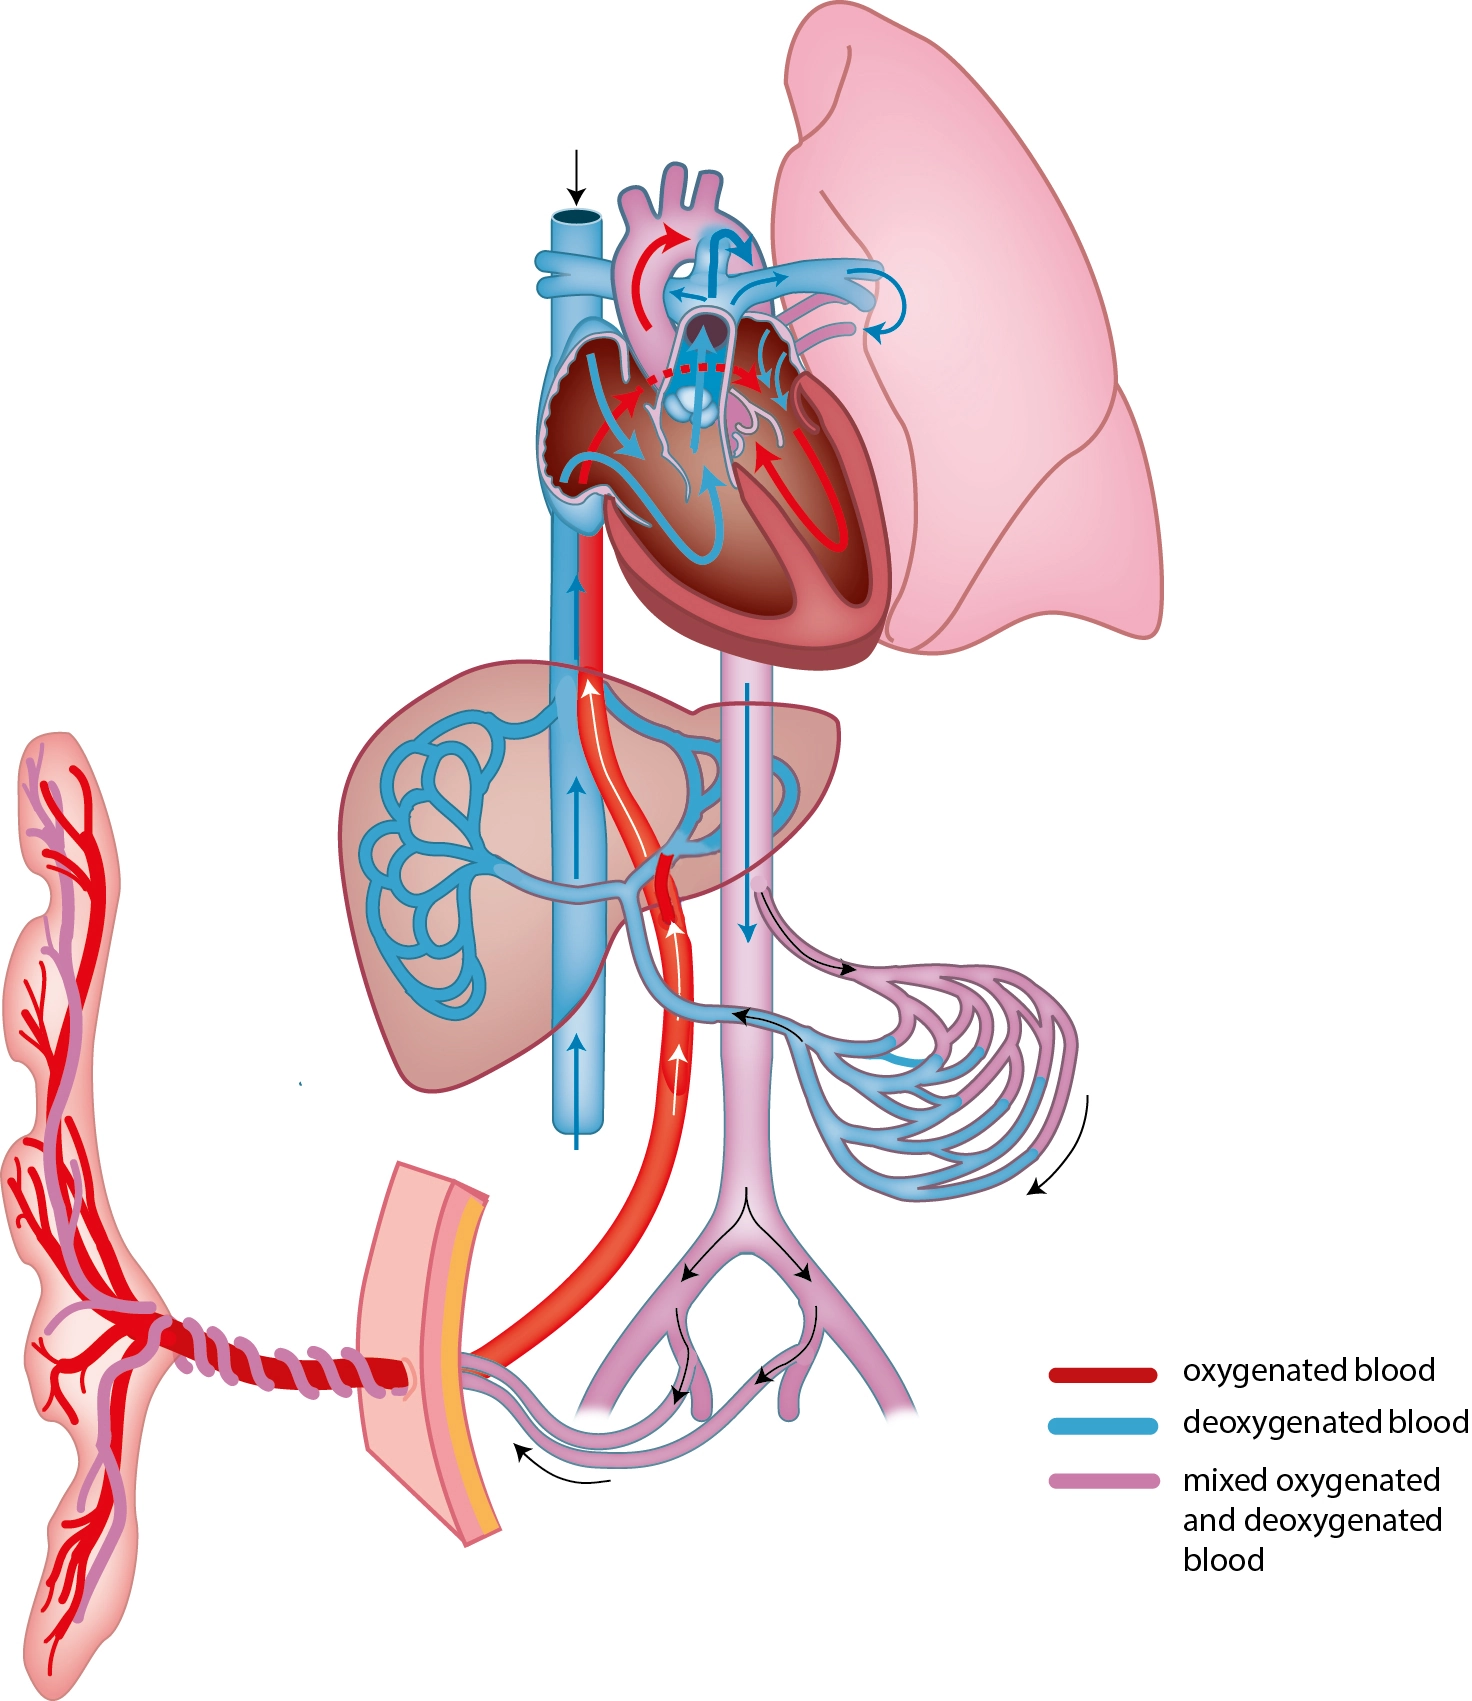

• Giải phẫu siêu âm mạch máu bụng thai quý I

• Bất thường mạch máu trong ổ bụng